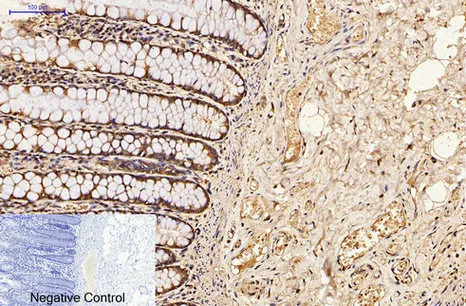

CDX2(14H6)Mouse Monoclonal Antibody

Cat: AMM08595

Size1:50μL Price1:$118

Size2:100μL Price2:$220

Size3:200μL Price3:$380

Application:WB,IF-P,IF-F,ICC/IF,IHC-P

Reactivity:Human,Mouse,Rat

Conjugate:Unconjugated

Optional conjugates: Biotin, FITC (free of charge). See other 26 conjugates.

Gene Name:CDX2